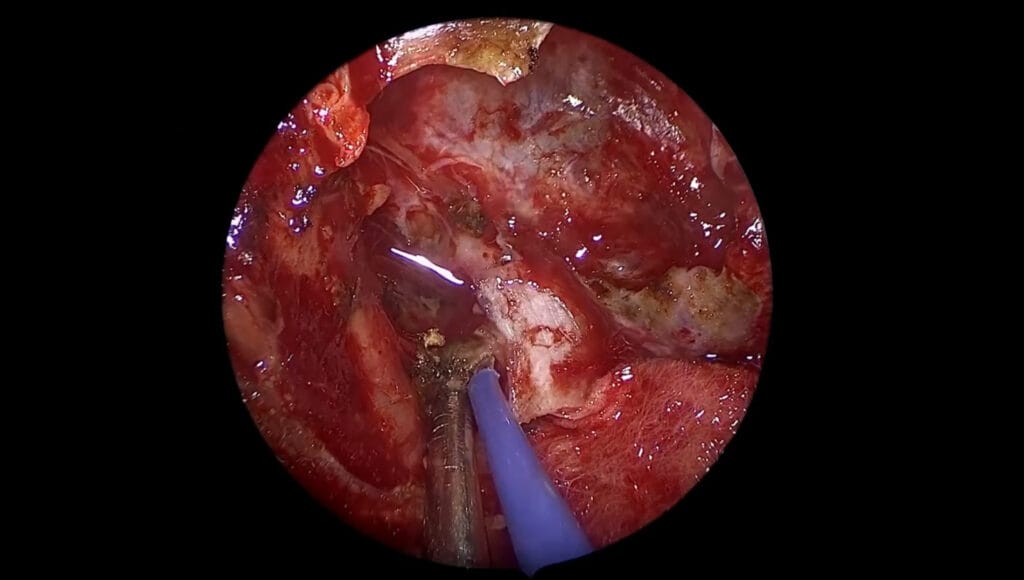

Cordoma clival: cirugía en dos tiempos

El Dr. Fernández-Miranda realiza la resección completa de un cordoma complejo de base de cráneo mediante dos cirugías complementarias: una vía endonasal endoscópica y una craneotomía orbitozigomática con petrosectomía anterior y abordaje trans-Meckel.